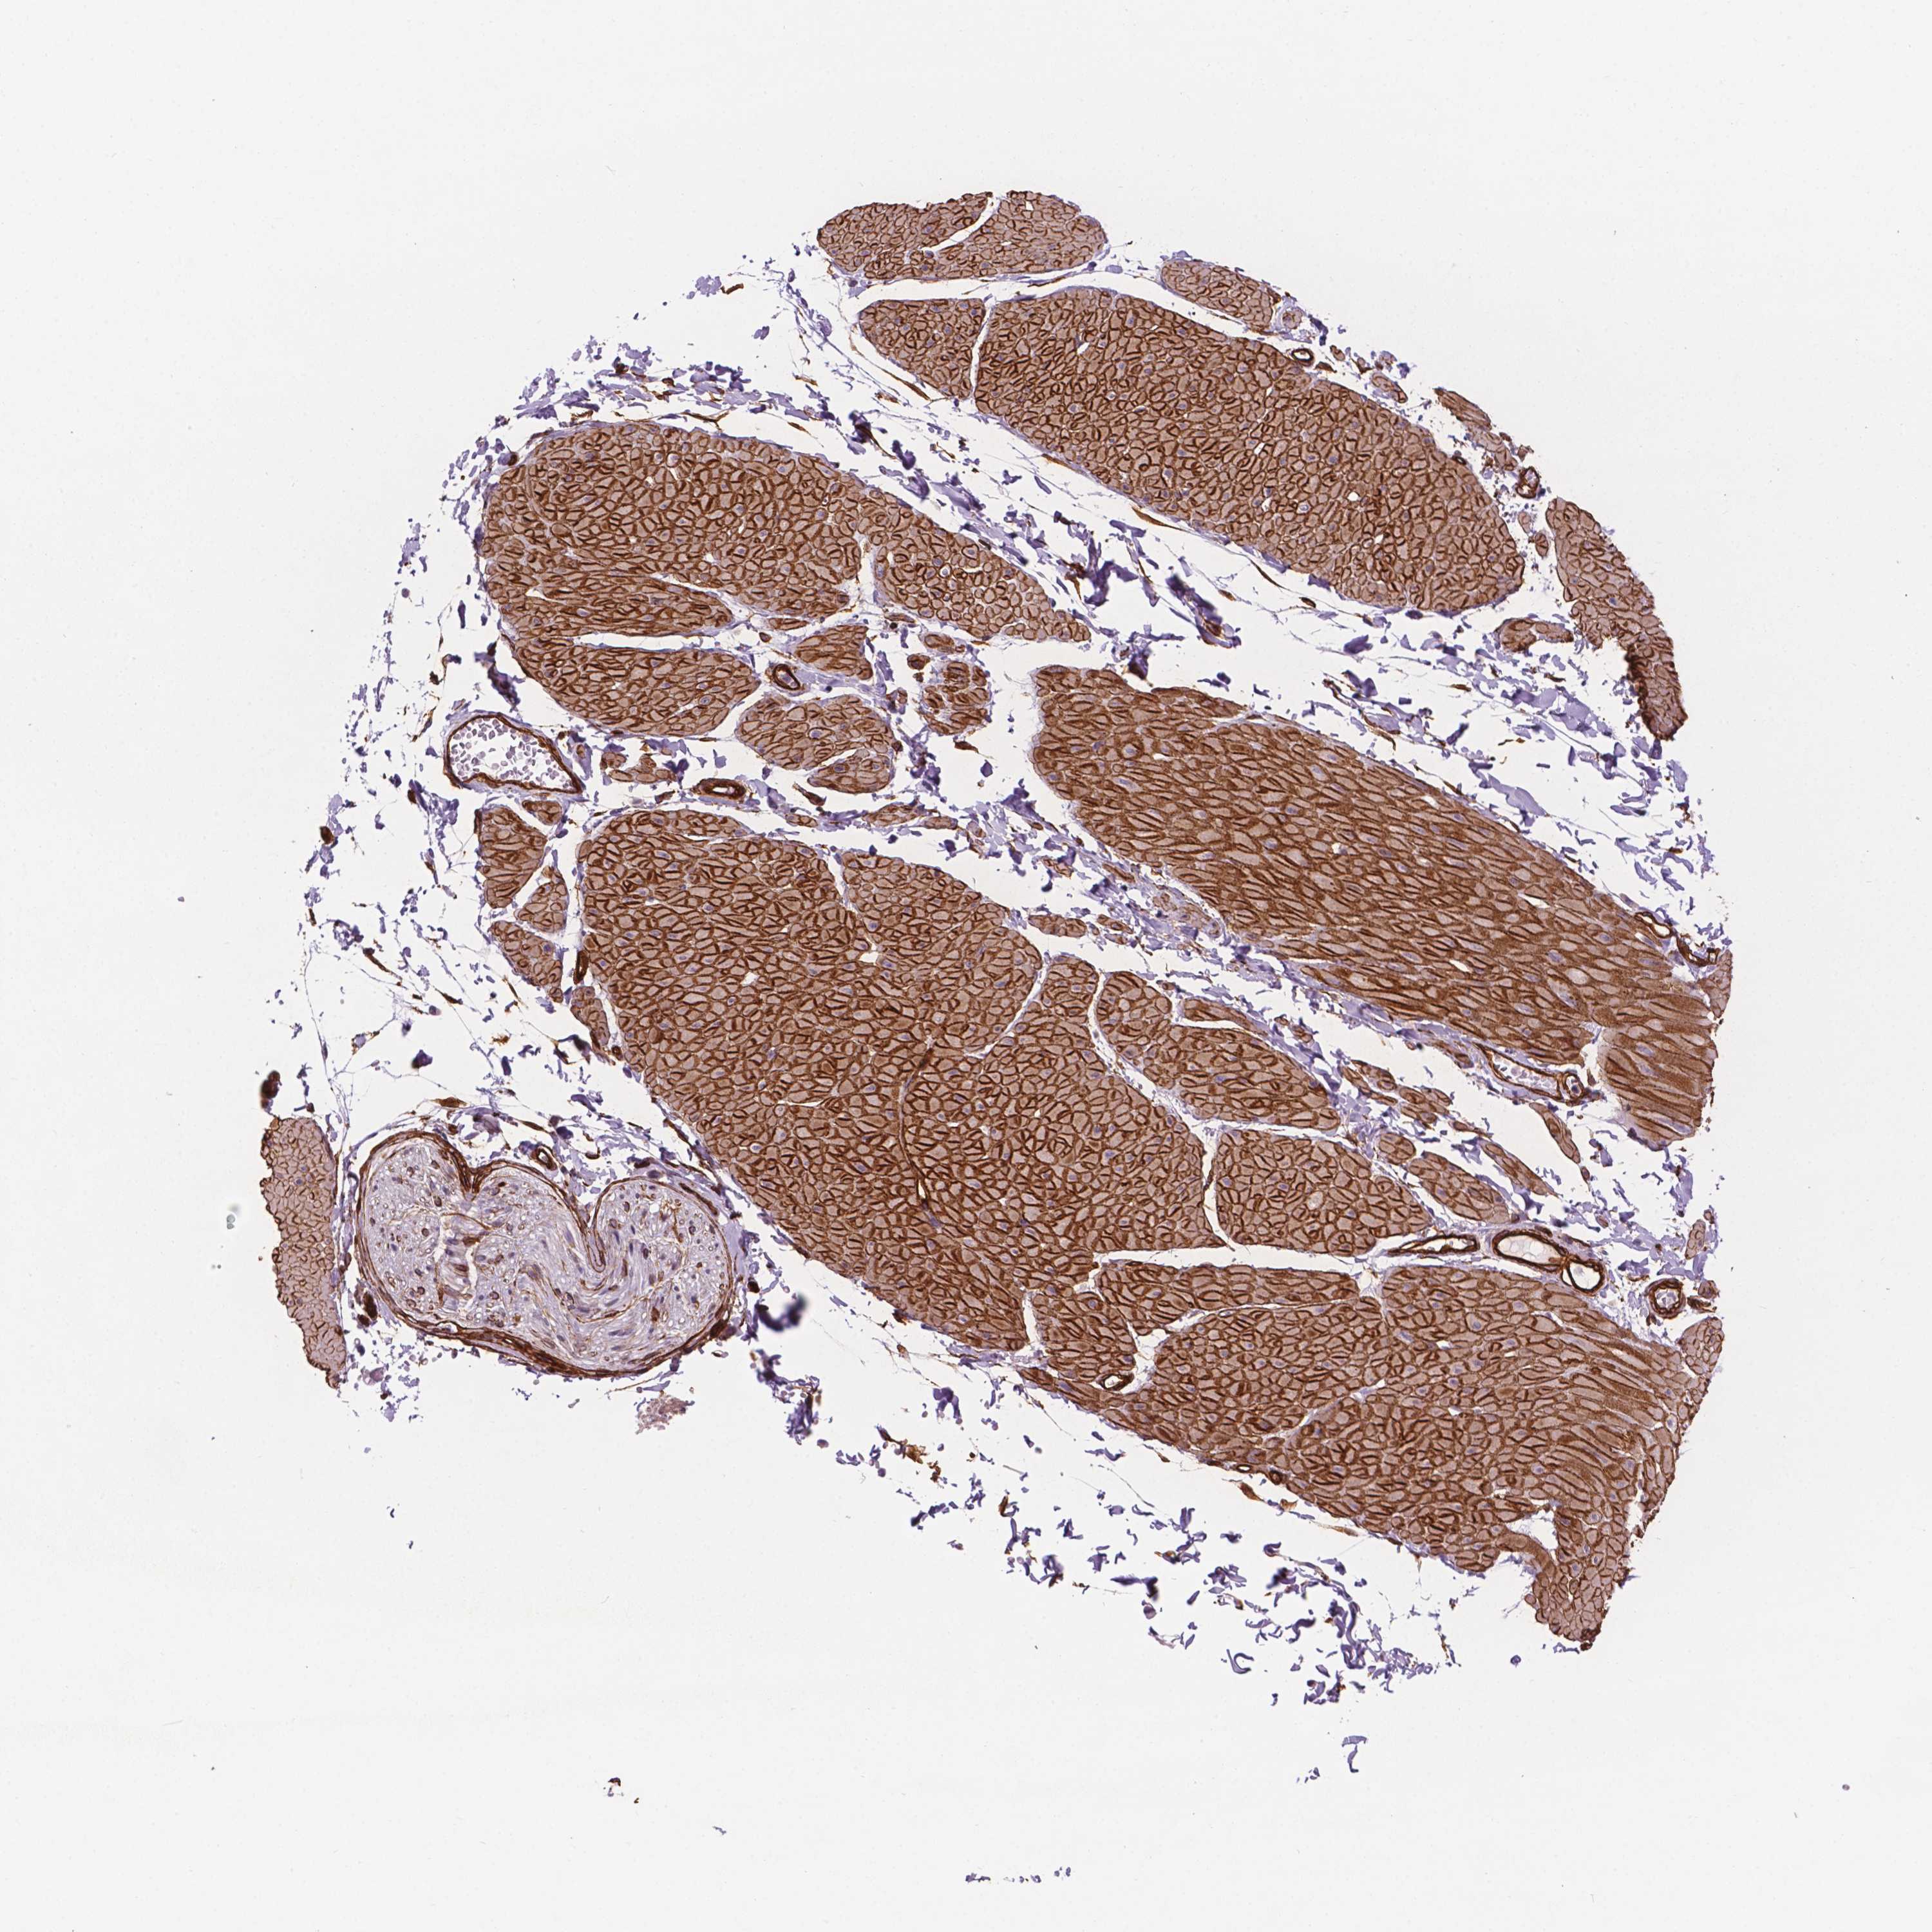

EGFL8